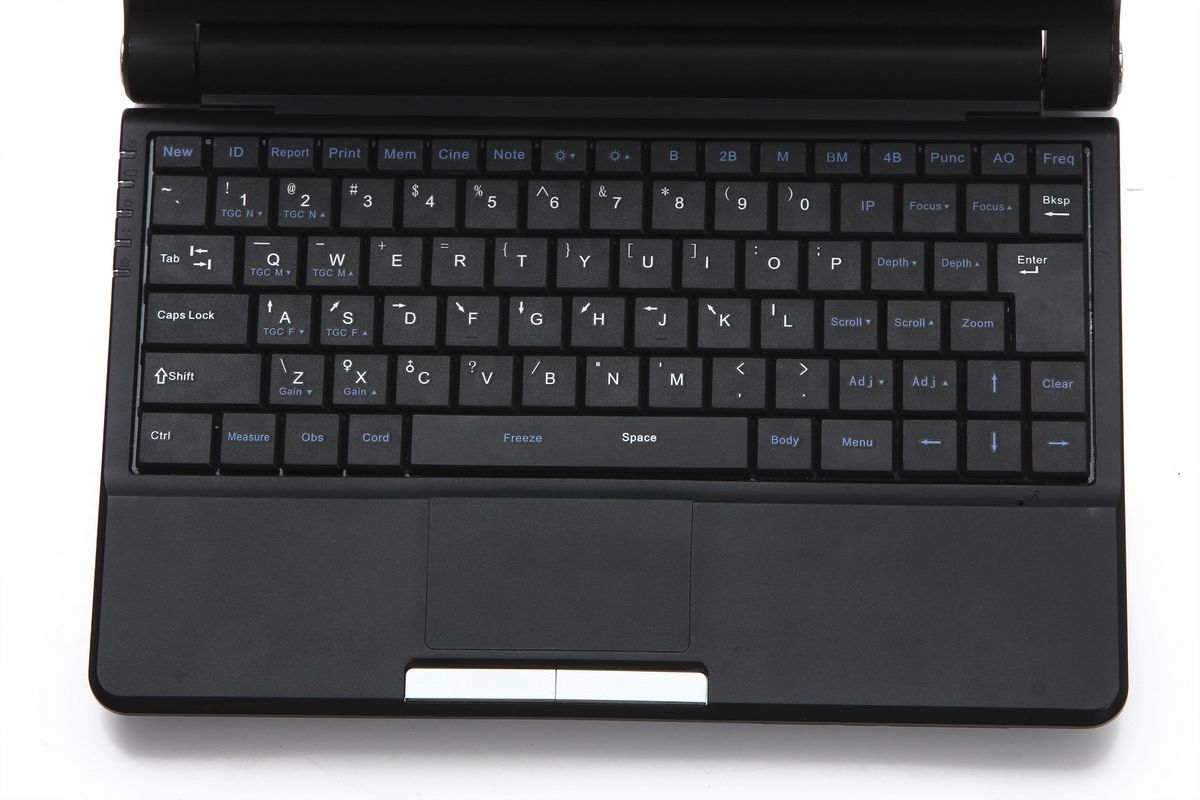

Portability and Ease of Use

Designed for ease of use, the Laptop Ultrasound scanner is lightweight and portable, allowing healthcare providers to conduct examinations in various settings. Whether in a clinic, hospital, or even at home, this device can be easily transported. Additionally, the intuitive interface simplifies the operation process, making it accessible for both seasoned professionals and newcomers, so more patients can benefit from timely diagnostics.